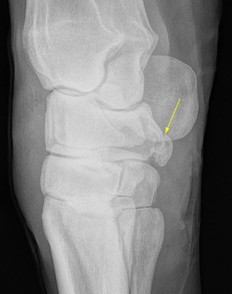

Proximal suspensory disease is a complex pathological process in horses that involves more than just the ligament itself. The bone component can, in some cases, be more clinically significant than the ligament injury. At the suspensory ligament enthesis – the complex attachment of the ligament to the bone surface – the bone can have sclerosis, fluid signal (“bone oedema”), resorption or avulsion fragments (image 1), and fissures of the proximal metacarpal bone can also be identified on MRI in this region (Murrey et al. 2020, Labens et al. 2020).